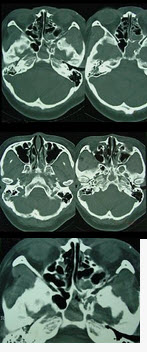

男,35岁,头部外伤后鼻腔有清亮液体流出,CT如图所示,最可能诊断()

A、颅底骨折伴脑脊液鼻漏

B、颅底骨折伴鼻窦积血

C、颅底骨折,鼻窦炎

D、外伤性颅底骨折

E、鼻窦炎伴鼻窦积脓

A